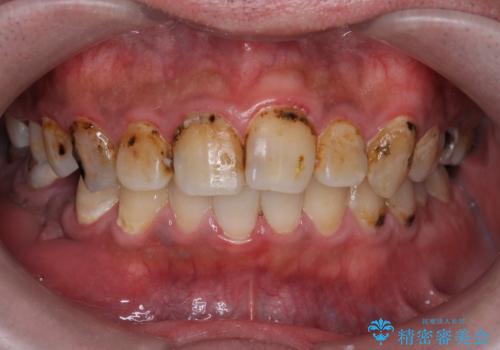

- 口の中をマスク生活の間に全て治したい、見た目を良くしたいとの事で来院。

まず徹底的に虫歯を取り除き、保存が出来ない部位は抜歯(親知らずを含む)を行い、根管治療が必要な部位は精密根管治療を行いました。

その後、インプラント治療、セラミック治療を行いました。

一度治療するはを全て仮歯に変えて、歯茎を整えてからセラミックを装着しました。

また、虫歯が歯肉の中まである場合はAPF(歯肉弁根尖側移動術)も行なっています。